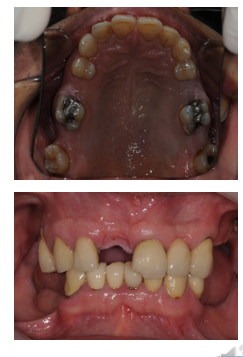

What is a conventional fixed-fixed bridge?

A fixed prosthesis where the pontic is supported by two abutments, one on each side.

conventional prep of abutment teeth: conventional crown

What are conventional cantilever bridges?

Bridges where the pontic is retained by a conventional crown, inlay, or onlay.

retention coming from 1 side only & conventional crown prep of that 1 abutment tooth

Q

Bridges where the pontic is retained by a metal retainer using cement and abutment coverage.

cantilver= one side only attachment

What is a cantilever bridge?

A prosthesis where the pontic is supported on one end by one or more abutments.